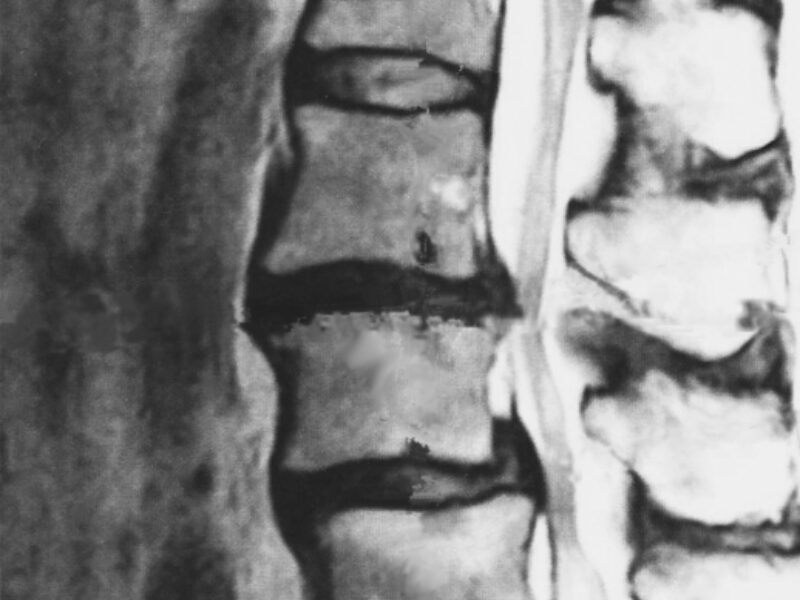

そもそも脊柱管狭窄症とは?

🦴脊柱管狭窄症とは?

脊椎の中を通る神経の通り道(脊柱管)が狭くなることで、神経が圧迫され、腰痛や足のしびれ、歩行困難などの症状が出る状態です。特徴的なのは、歩くと足がしびれてきて休憩が必要になる「間欠性跛行」という症状です。ただし、これは「結果」であって「原因」ではありません。長年の姿勢の悪さにより、筋肉が引き伸ばされ、その中にある血管や神経も引き伸ばされた結果、血流が悪くなって神経を栄養できなくなり、炎症が起きて痛みやしびれが現れているのです。